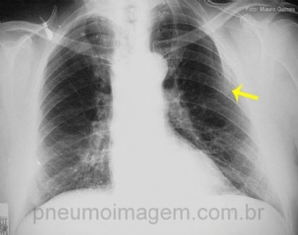

CASO CLÍNICO #34

Paciente se apresenta com dispneia. Você acha que a lesão apontada pela seta é a causa do sintoma? Deixe seus comentários abaixo. ***** Patient has dyspnea. Do you think the lesion of the arrow is the cause of the symptom? Write your comments below.